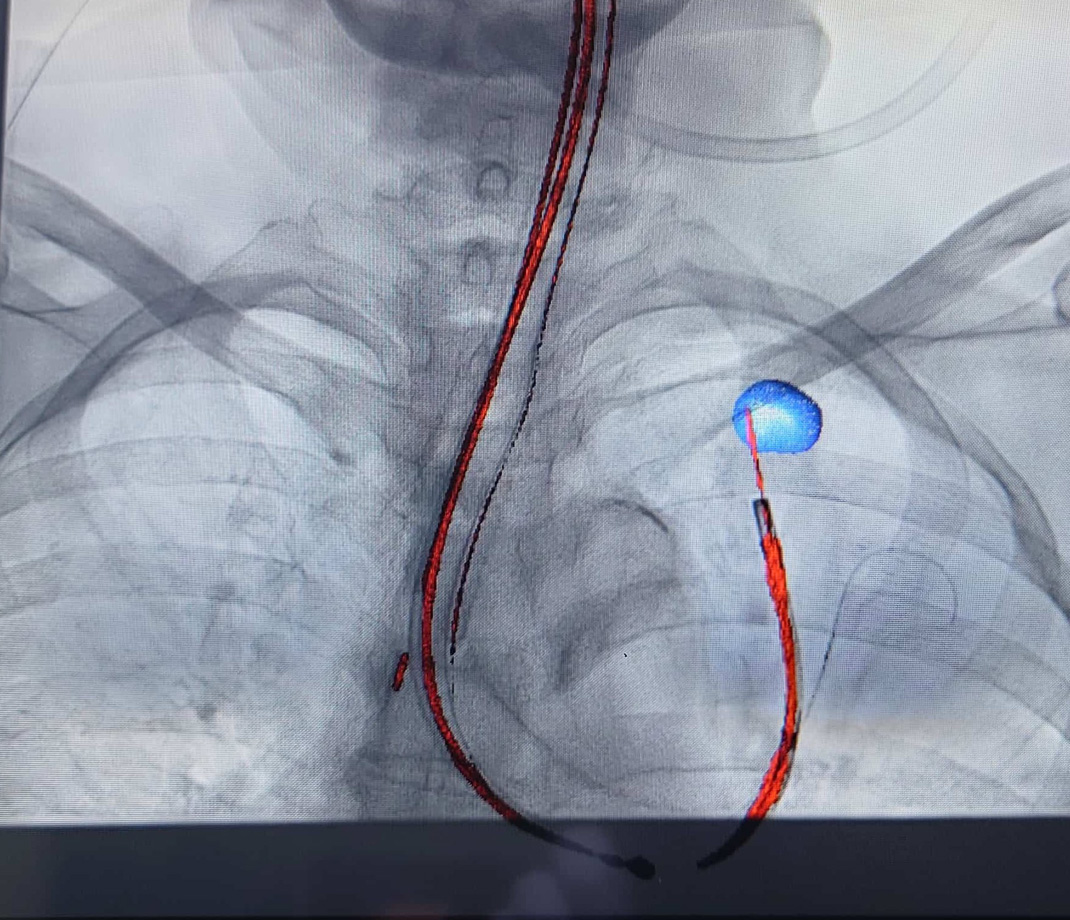

当科では、症例に応じて、従来の約半分の太さ(外径3.0mm)の極細径気管支鏡(図1)を使用しています。さらに、CT検査から作成した病変までの立体的ガイドマップを用いる「仮想気管支鏡ナビゲーション」(図2a, b,c)により、短時間でより正確な気管支鏡検査が可能です。この方法は浅野部長が考案したもので、2003年度日本呼吸器内視鏡学会賞を受賞しています。2025年にはNHK「あしたが変わるトリセツショー」でも紹介されました(NHKオンデマンドシーズン1,エピソード38 新「がん対策」のトリセツ!命を守る切り札SPで視聴可能)。現在は保険診療の適応となっています。

また、早期末梢型肺癌の診断精度向上のため、当科では超音波をルーチンに併用し、必要に応じてクライオ生検も行っています。さらに、2cm以下の小型病変に対しては、全国に先駆けてコーンビームCTを併用した気管支鏡検査を実施しています(図3)。これらの手法を組み合わせることで、従来は気管支鏡の適応外とされていた、X線で描出されにくい微小病変の診断も可能となり、高い診断率を得ています。

図2-c図2 仮想気管支鏡ナビゲーション:検査前に設定した病変(青い丸)への気管支ルート(青い線)が青線で表示されるので、これに従い気管支鏡を挿入します。